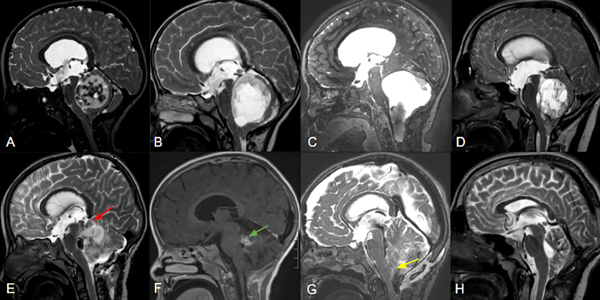

Los tumores centrales se definieron como aquellos emergiendo del vermis/paravermis o localizados en el IV ventrículo. Los tumores originados en un hemisferio cerebeloso con crecimiento medial y compresión del IV ventrículo no entran en esta categoría. (Figura 1)

Los tumores sólidos se categorizaron como lesiones cuyo componente sólido corresponde a más del 90% de su naturaleza. Se englobaron las lesiones quísticas independientemente de su presencia o ausencia de nódulo mural o componente sólido. (Figura 1,2)

Figura 1. Imágenes ilustrativas de RM ponderadas en T1 (A,D), T1+ gadolino (B,E) y T2 (C,F), comparando una lesión predominantemente hemisférica y quística con efecto de masa y desplazamiento troncal (flecha roja) (A;C), con otra central y sólida con invasión troncal (flecha amarilla) (D:F). En el primer caso es más factible lograr la RT y menor riesgo de requerimiento de manejo post operatorio de hidrocefalia o recurrencia, mientras que en el segundo presenta un mayor riesgo de RST, mutismo y necesidad de manejo postoperatorio de hidrocefalia o recurrencia.